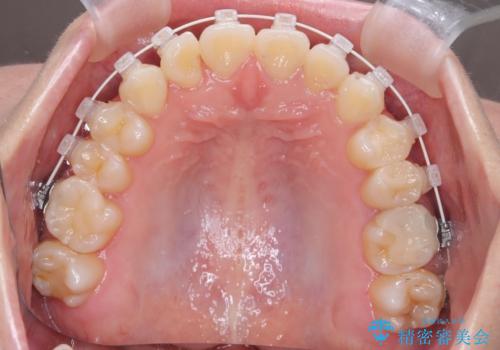

インビザラインを希望されておりましたが、20時間もつけることができなかったためワイヤー矯正にて叢生の改善を行っています。

右上の側切歯(前から2番目の歯)が90度程度ねじれている状態でしたが、1月に1回のワイヤー交換できれいに並ぶことができ満足いただけました。

捻れた歯の治療に関しては、ワイヤー矯正の方が仕上がりがきれいに治りやすいです。